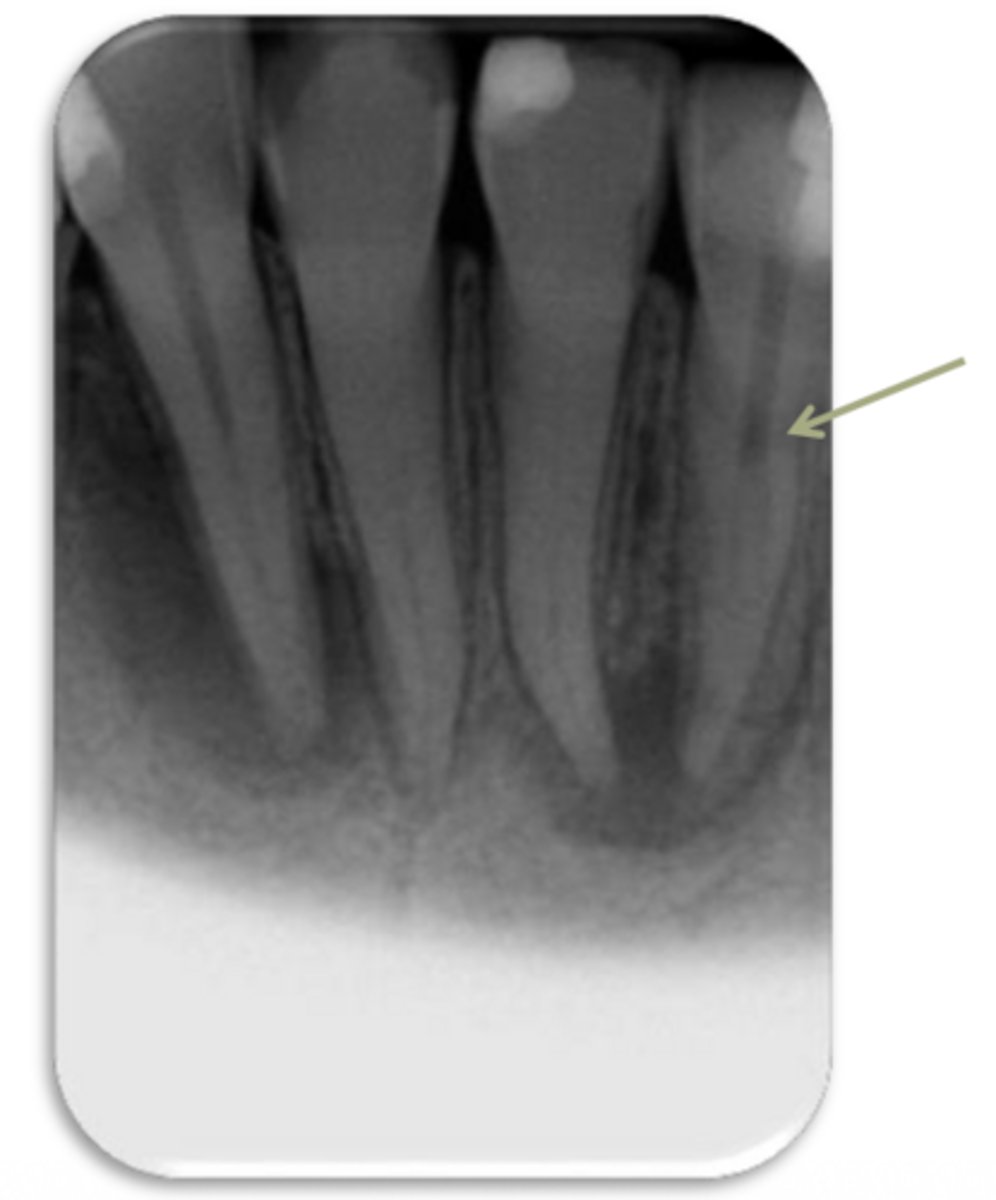

ID the problem:

external resorption